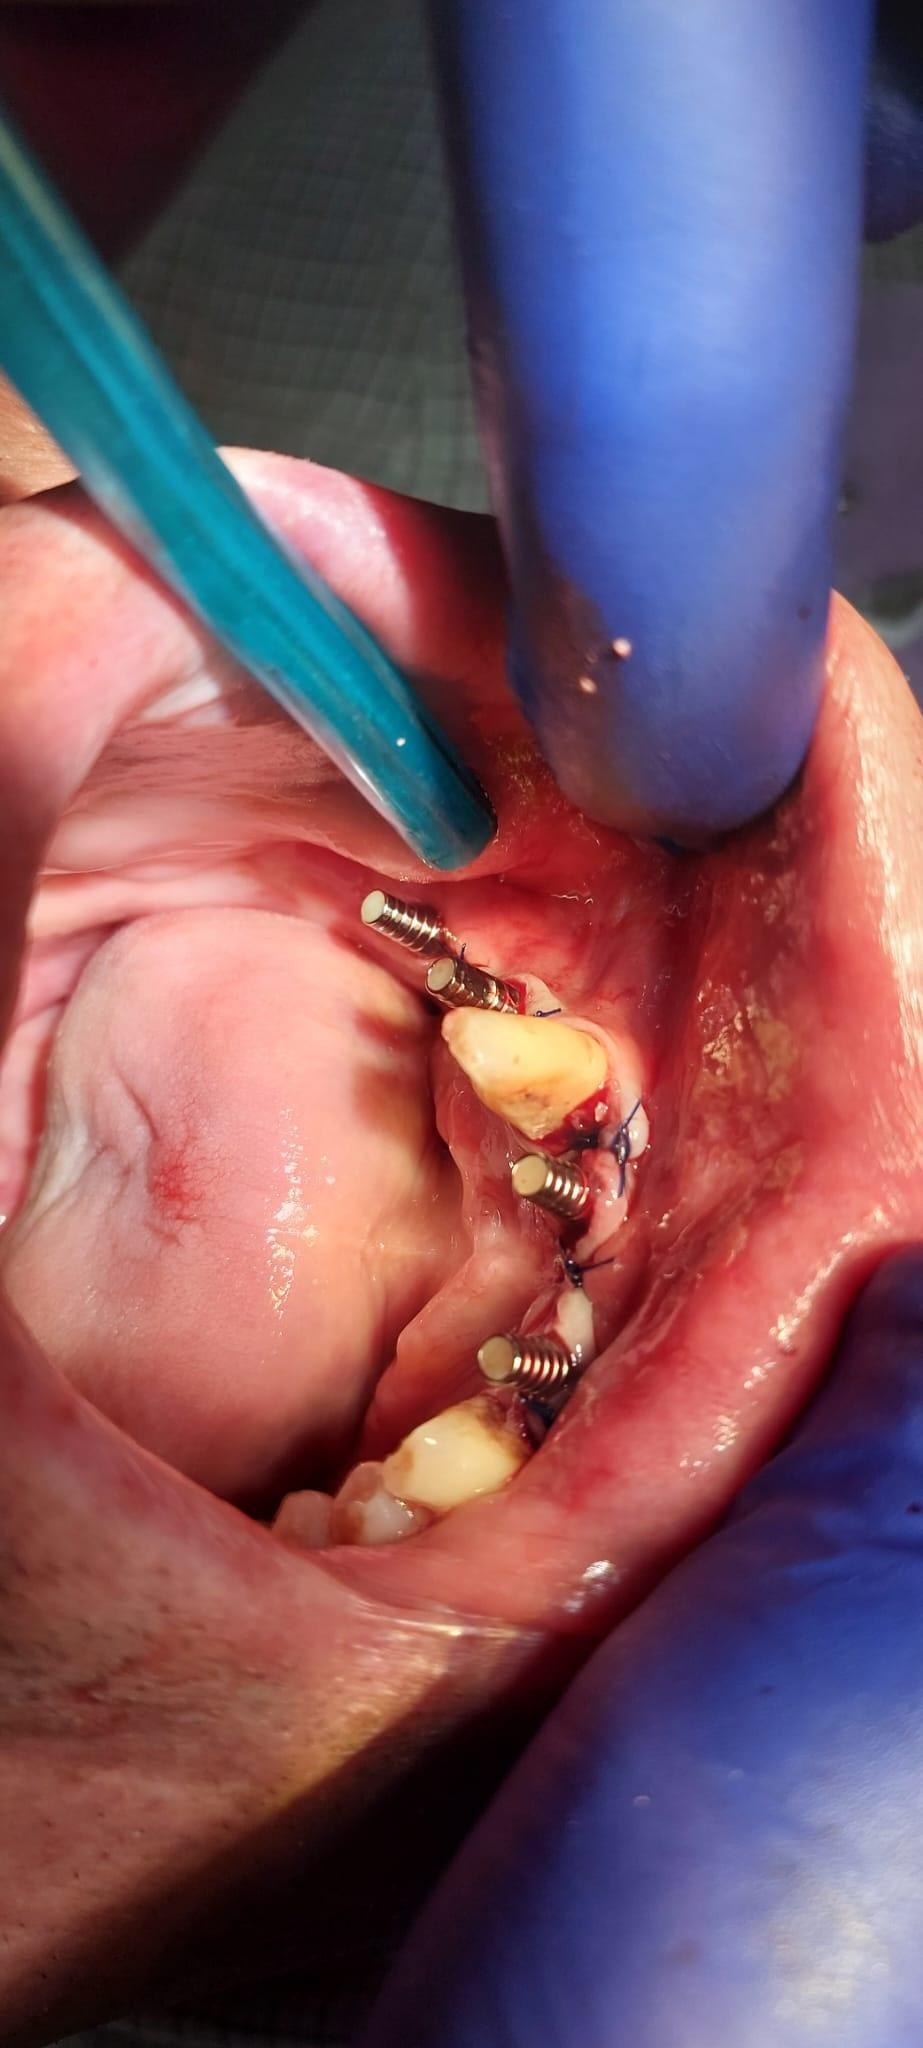

Boala parodontala are un caracter progresiv. Pentru cazurile mai grave, recomandam tratamentul parodontal chirurgical rezectiv sau regenerativ.